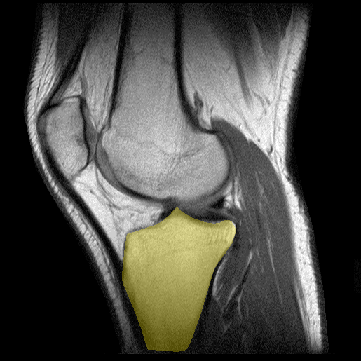

TIBIA

Definición: La tibia es el hueso más fuerte de la parte inferior de la pierna.

Origen: la tibial proximal se divide en los cóndilos medial y lateral. La superficie proximal de la tibia, que se articula con el fémur comprende dos facetas: la anteroexterna (facies fibularis) es ligeramente concava en tanto que la anterointerna (facies tibialis) es algo convexa, lisa y está situada inmediatamente for debajo de la piel. Las partes centrales de las facetas tibiales alojan los cóndilos femorales. Los bordes de las facetas tibiales sirven como puntos de anclaje de los respectivos meniscos. La protuberancia intercondilar (espina de la tibia) representa una elevación entre las dos facetas articulares y está limitada por los tubérculos interno y externo.

Inserción: Los tubérculos tibiales sirven de puntos de anclaje del ligamento patelar. El tubérculo de Gerdy, sobre la superficie anterolateral de la tibia proximal sirve para la inserción del tracto iliotibial. Además, los tendones sartorius, gracilis y semitendinoso -los tendones del pes anserinus -- se insertan en la tibia anteromedial proximal tibia. El tendón semimenranoso se inserta en el margen posteromedial de la tibia proximal.